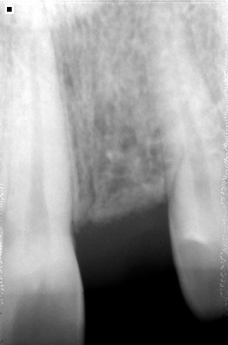

El proceso de utilizar implantes inicia con un completo examen clínico y por imágenes de nuestros pacientes para determinar el estado de salud bucal y dental (dientes, encías, hueso alveolar, etc.) y salud en general con el fin de obtener un diagnóstico y plan de tratamiento seguro, cómodo y duradero.

Cuando la falta de todos los dientes ha hecho que el hueso pierda volumen, la solución más apropiada es una prótesis híbrida.

El proceso se inicia con seis puntos de apoyo que actuarán como base fija de la prótesis. Consisten en implantes dentales de titanio biocompatible que unen la estructura al hueso.

Luego fijamos a los implantes una prótesis con base metálica y estructura de resina, con todas la piezas dentales.